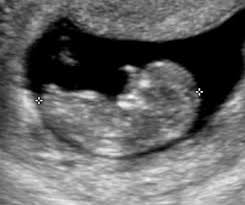

Vue de côté, le bébé regarde vers le haut, en blanc les os. Identifier les anomalies structurelles l'échographie morphologique peut détecter. L'échographie est une technique d'imagerie non irradiante utilisant les ultrasons qui sont émis par une sonde que le médecin radiologue pose sur la peau.